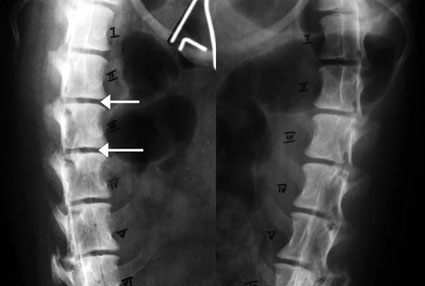

写真下段: 手術時の写真

中央を横に走るのが、硬膜を切開して露出した脊髄神経(黄色三角で示す)です。背側に出血による変色部(黄色矢印)がみられます。ピンセットでつまんでいるのは、切開した硬膜です。

硬膜切開によって、脊髄神経をとりまく血管の血流は改善し、色調も改善しました。

ハンセンII 型症例の術中写真で、皮膚部分(緑色三角で示す)が光を反射して見えるのは、

インサイズドレープを貼り付けてあるからです。 |